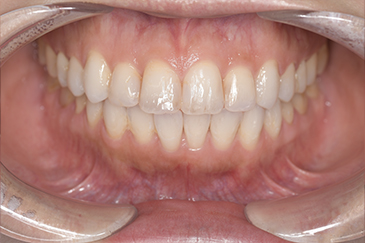

Before

After

基本情報

| 主訴 | 見た目をきれいにしたい |

| 治療期間 | 6ヶ月 |

| 治療費 | ジルコニアボンド(セラミックの被せもの)¥165,000×7(税込み) オフィスホワイトニング4回 ¥4,400×4(税込み) ホームホワイトニング¥11,000 |

| リスク・副作用 | かみ合わせがとても強い方の場合、稀に割れてしまうことがあります。 |

| 先生からの提案 | 上の前歯6本と右下の2番目の歯はセラミックの被せもので治療。 残りの下の前歯5本はプラスチックの材料で虫歯を治療し、 ホワイトニングをおこないました。白くなったご自身の歯の色に合わせてセラミックの 被せものを作成しています。 模型上で完成後をシュミレーションし、上の歯茎の位置をきれいに見えるように 揃えています。(外科処置はしていません) |